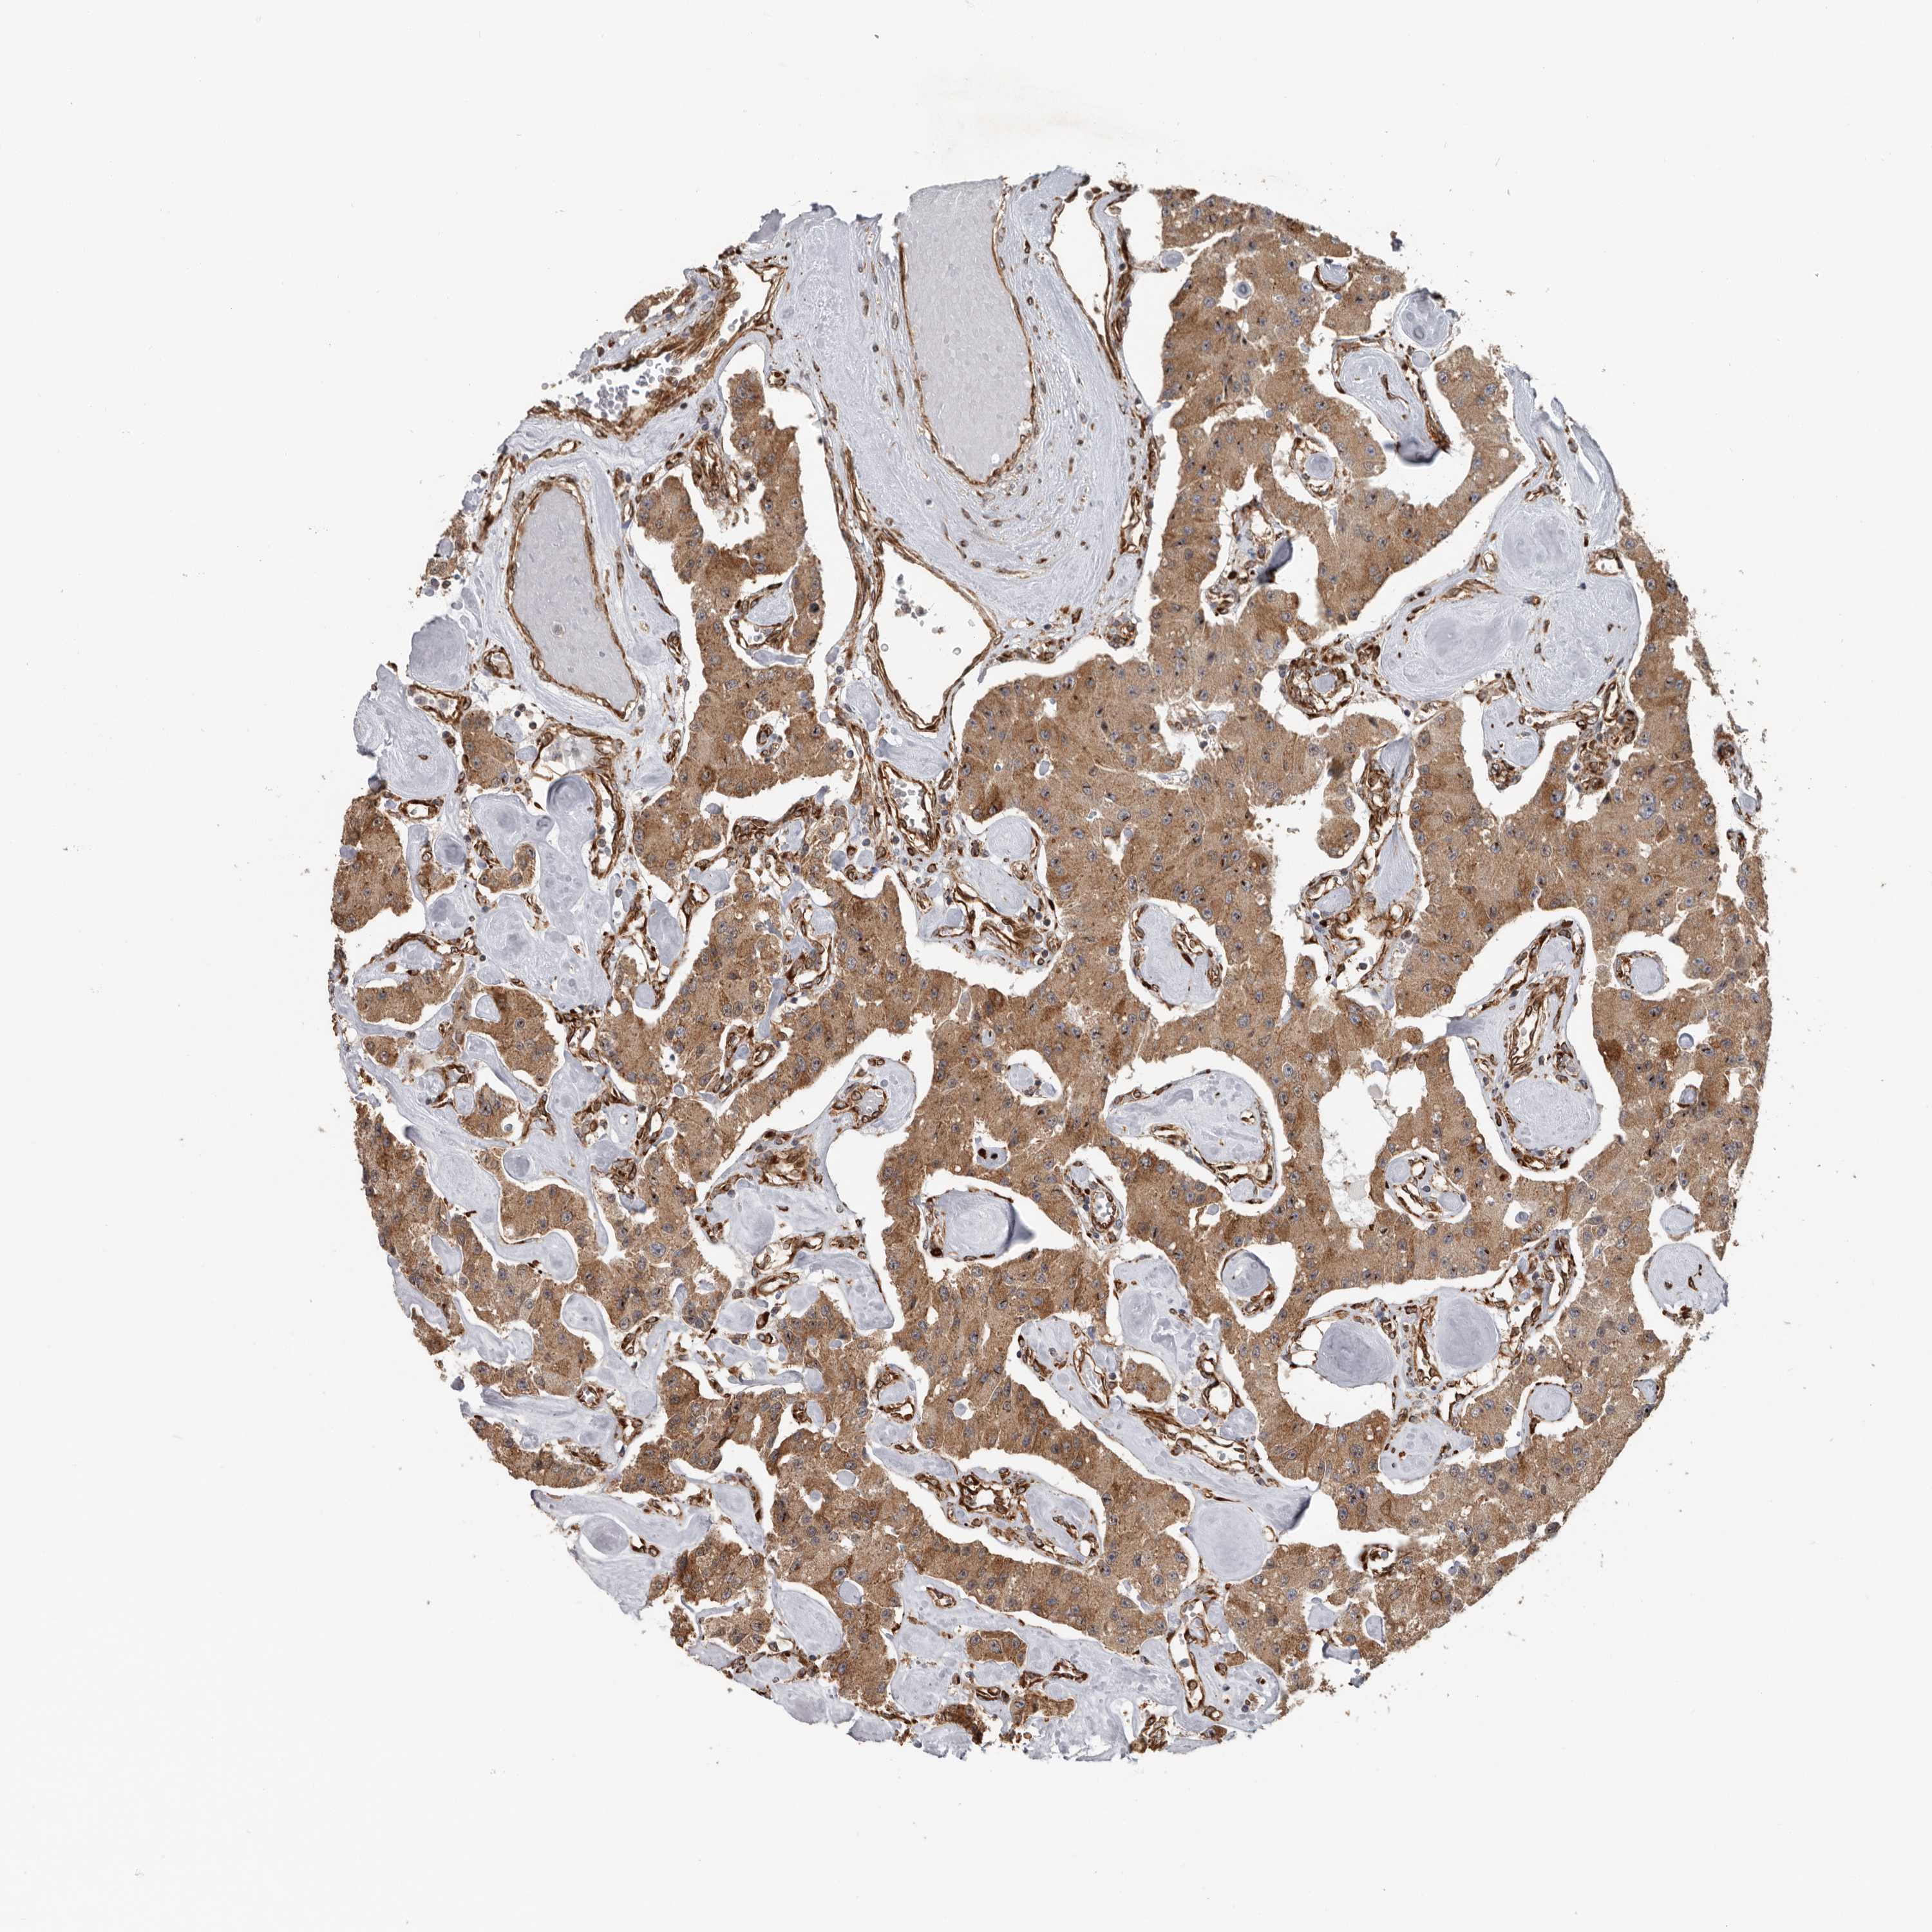

CARCINOID - Protein expressioni

A mouse-over function shows sample information and annotation data. Click on an image to view it in a full screen mode. Samples can be filtered based on level of antibody staining by selecting one or several of the following categories: high, medium, low and not detected. The assay and annotation is described here.

Antibody stainingi

Antibody staining in the annotated cell types in the current human tissue is reported as not detected, low, medium, or high, based on conventional immunohistochemistry profiling in selected tissues. This score is based on the combination of the staining intensity and fraction of stained cells.

Each image is clickable and will lead to virtual microscopy that enables deeper exploration of all samples and also displays staining intensity scores, fraction scores and subcellular localization as well as patient and tissue information for each sample.

Antibody HPA028355

Antibody HPA028357

Staining

High

Medium

Low

Not detected

Intensity

Strong

Moderate

Weak

Negative

Quantity

>75%

75%-25%

<25%

None

Location

Nuclear

Cytoplasmic/membranous

Cytoplasmic/membranous,nuclear

Carcinoid, malignant, NOS

Carcinoma, NOS